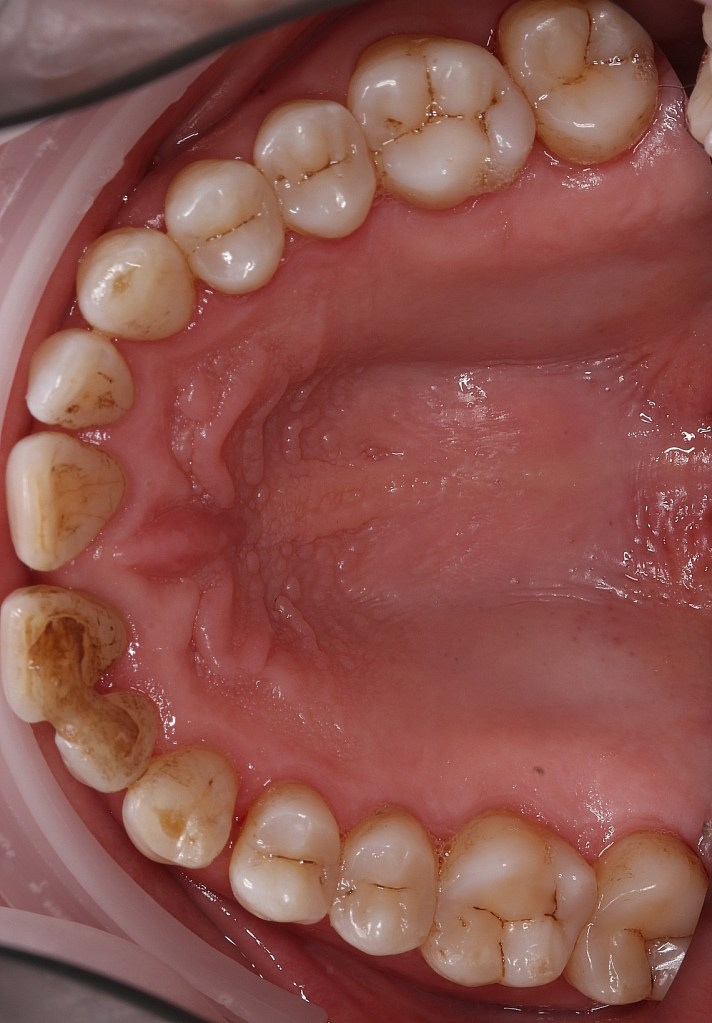

Atașez pozele unui pacient care până la vârsta de 44 ani nu a fost niciodată la dentist, cu reflex de vomă exagerat și igienă deficitară, speriat că i s-a propus extracția a peste 50% din dinți din cauza mobilității generalizate de gradul II și III. Am mers pe varianta clasică, debridare parodontală nechirurgicală, la microscop, cu anestezie locala în toate cadranele, realizată într-o singură ședință. Am administrat antibiotic pe cale generală și am urmărit respectarea indicațiilor de igienă prin controale lunare. Rezultatele la 6 luni vorbesc de la sine, acum putând să ne ocupam liniștiți de regenerarea defectelor osoase de la nivelul 21 22, de altfel singurii dinți care mai au mobilitate.

Iar retracția de la 31 s-a vindecat singură 🙂 Pentru că timpul e, uneori, cel mai bun tratament.